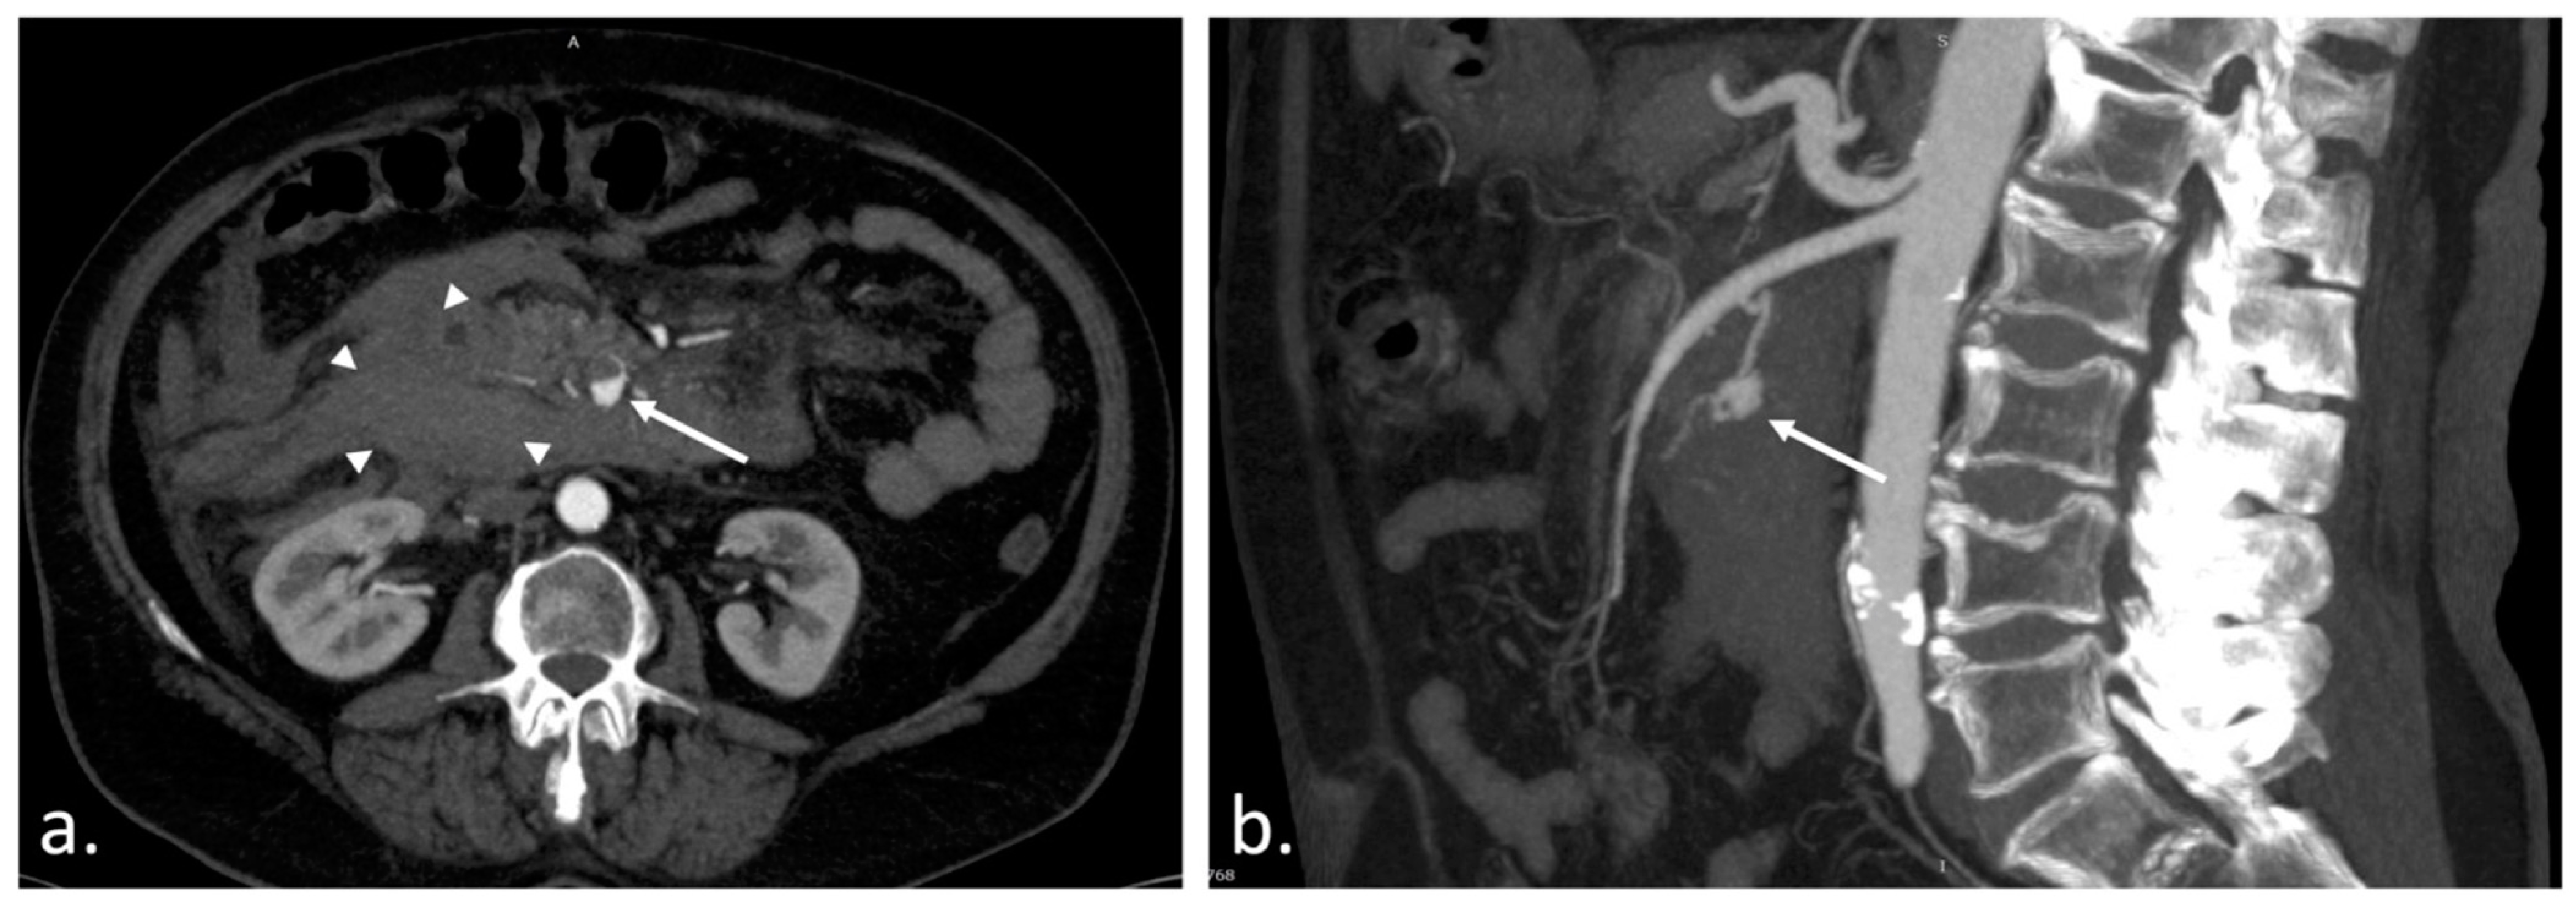

Figure 1. Aneurysmal dilatation of visceral arteries occurs in less than 1% of arterial aneurysm cases [1,2], primarily affecting the splenic artery, hepatic artery, and superior mesenteric artery; in only 1–2% of visceral aneurysms, it is found in the pancreaticoduodenal or gastroduodenal artery [1], with a high mortality rate in untreated cases [2,3,4]. Arterial aneurysmal dilatation develops as a result of damage to the collagen structure at the arterial wall caused by atherosclerosis or hypertension, and is found with the highest incidence at the level of the abdominal aorta [5,6,7,8,9]. In contrast, arterial pseudoaneurysms are connected with trauma, surgical treatments, or the presence of malignancies, but in the case of the pancreaticoduodenal artery, the main reason is the association with chronic pancreatitis [9,10,11,12,13,14,15,16]. Although it is a rare pathology, it is lethal in the absence of intervention. Endovascular treatment is currently the primary approach in the event of these pathologies, with a high success rate and excellent patient progression [4,9,13,14,15,16,17,18,19,20,21,22,23]. A 67-year-old woman presented with lightheadedness, diaphoresis, and acute epigastric and right hypochondrium pain. Along with other antecedents, her past medical history includes stage 2 essential hypertension, chronic ischemic cardiomyopathy, and class 1 obesity. Furthermore, three weeks before her current admission, she experienced a SARS-CoV-2 infection. She has no history of alcohol abuse, smoking, or abdominal trauma. An abdominal contrast-enhanced CT scan showed an extensive hematoma (3 × 4 cm2 in size) located intra-abdominally, adjacent to the duodenojejunal area, with hyperdensity around the duodenum and inferior to the pancreas (30–59 HU). Moreover, the CT scan also revealed an enhancing lesion as a pseudoaneurysm of the inferior pancreaticoduodenal artery measuring 5 × 8 × 8 mm3 with active bleeding and an associated hematoma. Additionally, the pancreas showed multiple hyperdense hemorrhagic structures anteriorly and superiorly under the aspect of possible acute hemorrhagic-ulcerative pancreatitis. Following these investigations of the abdominal area, a decision was made to proceed with an endovascular intervention within the interventional radiology department. (a) Transverse CT angiogram image shows a 12 mm enhancing lesion (white arrow) and a large intraperitoneal hematoma (arrowheads); (b) Sagittal MIP image depicts the enhancing lesion as a pseudoaneurysm (white arrow) of the inferior pancreaticoduodenal artery, responsible for the bleeding.